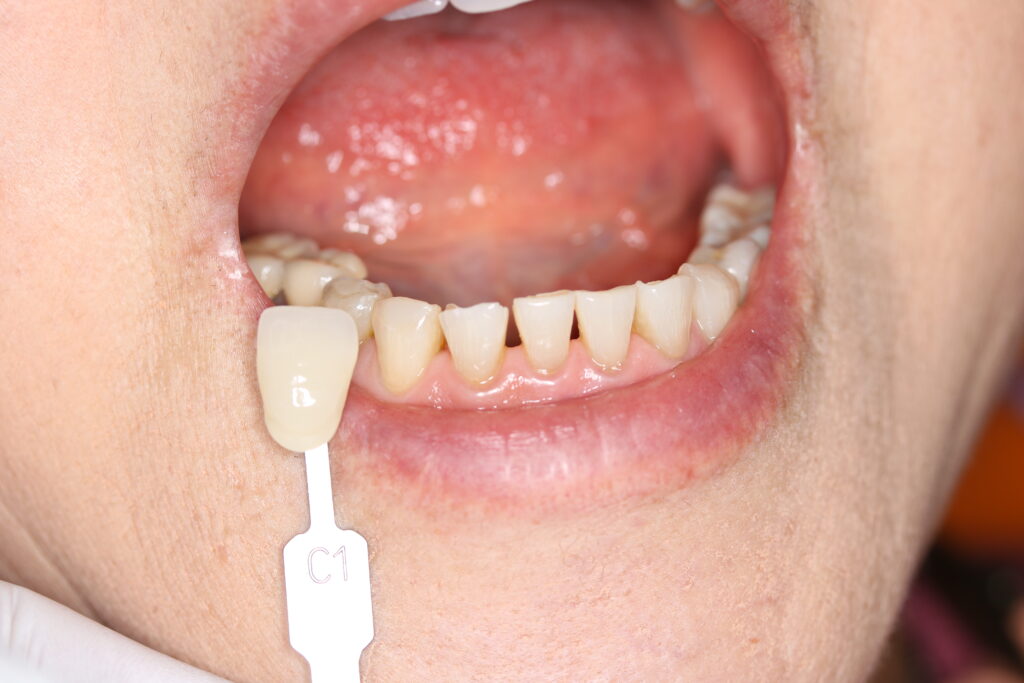

■色合わせ(シェードテイク)

最終的な見た目が自然になるよう、歯の色合わせを慎重に行いました。

患者さまの肌色や口元の印象に調和する色を選択し、違和感のない自然な仕上がりを目指しています。